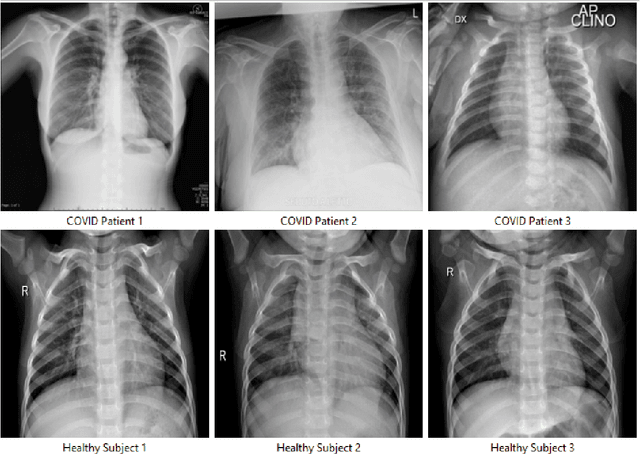

Abstract:In a hyperconnected environment, medical institutions are particularly concerned with data privacy when sharing and transmitting sensitive patient information due to the risk of data breaches, where malicious actors could intercept sensitive information. A collaborative learning framework, including transfer, federated, and incremental learning, can generate efficient, secure, and scalable models while requiring less computation, maintaining patient data privacy, and ensuring an up-to-date model. This study aims to address the detection of COVID-19 using chest X-ray images through a proposed collaborative learning framework called CL3. Initially, transfer learning is employed, leveraging knowledge from a pre-trained model as the starting global model. Local models from different medical institutes are then integrated, and a new global model is constructed to adapt to any data drift observed in the local models. Additionally, incremental learning is considered, allowing continuous adaptation to new medical data without forgetting previously learned information. Experimental results demonstrate that the CL3 framework achieved a global accuracy of 89.99\% when using Xception with a batch size of 16 after being trained for six federated communication rounds.